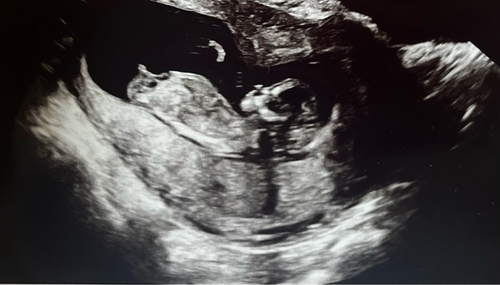

Hi! Wat denken jullie :)?